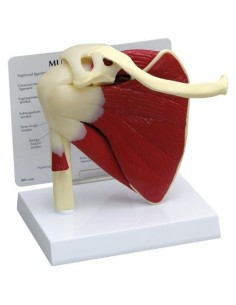

Dal cranio in 22 parti con incastri magnetici ai modelli di colonna vertebrale, da quelli di articolazioni a quelli di cuore, ogni pezzo della nostra collezione è progettato per un’immersione totale nello studio dell’anatomia umana. I nostri modelli, realizzati tramite scansioni di ossa vere, garantiscono un’esperienza tattile autentica e una fedeltà di peso quasi identica agli originali.

Essenziali per studenti e professionisti, i nostri modelli anatomici sono strumenti didattici che permettono di osservare le strutture anatomiche con precisione, eliminando la necessità di dissezioni o studi invasivi. Sono inoltre utili per spiegare ai pazienti le patologie, rendendo la comunicazione più efficace e risparmiando tempo prezioso.